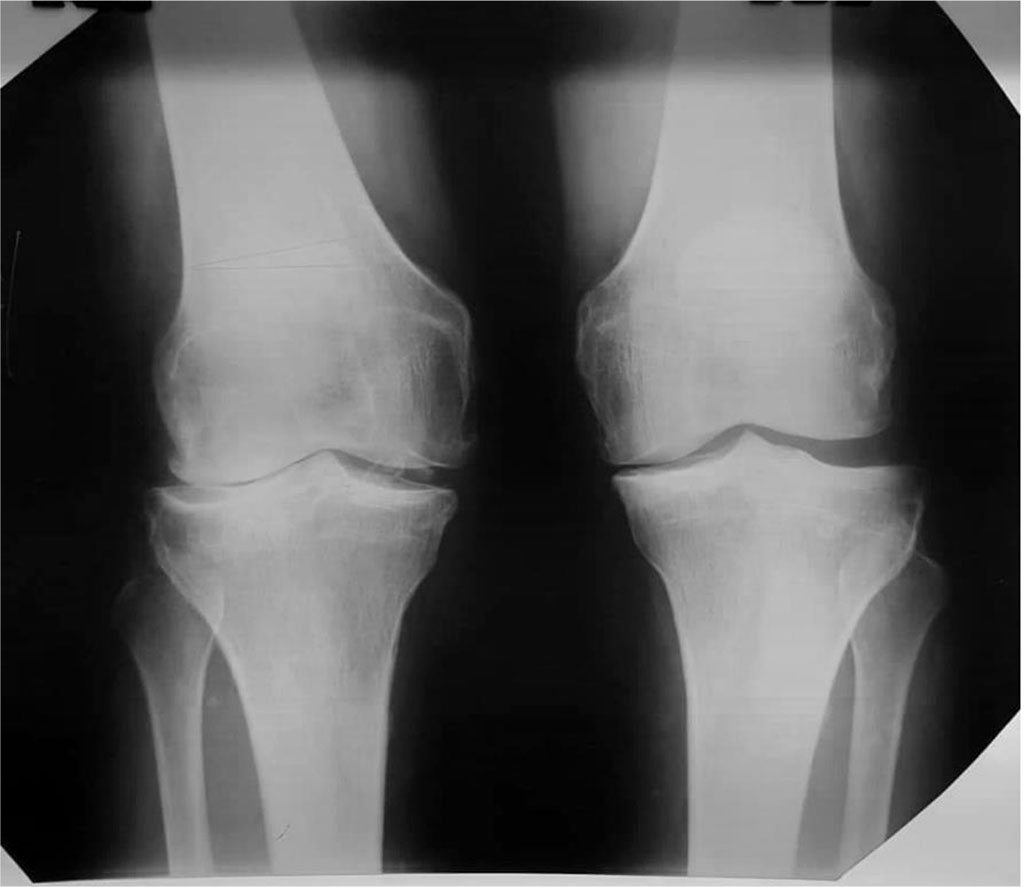

Patient T. is 48 years old. He referred to the clinic with complaints of pain and deformity in the right knee joint. At the time of reference, several clinical trials were conducted, according to the results of which the patient was diagnosed with: bilateral gonarthrosis of the III stage with valgus deformity on the right and varus deformity on the left (Fig. 2).

Figure 2. Radiographs of the knee joints before the operation in the loaded state.